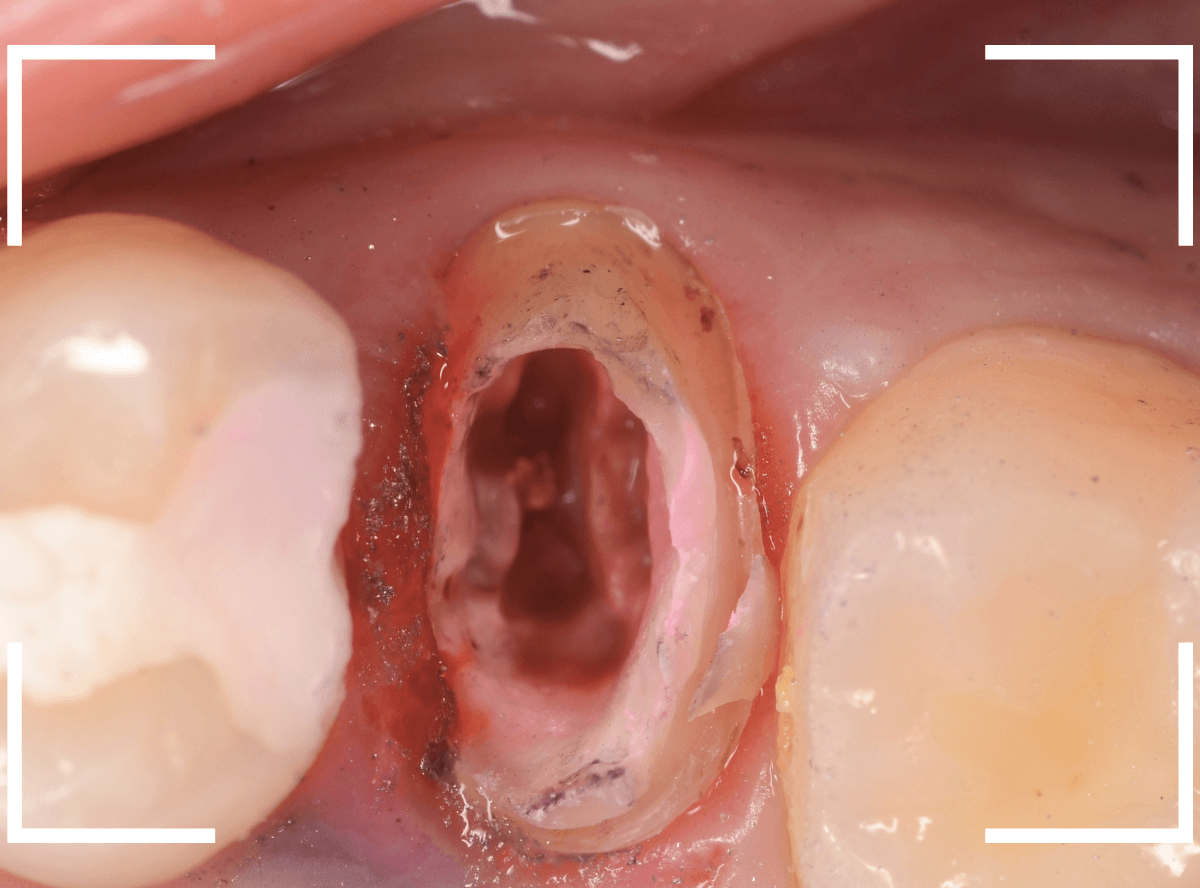

一番奥の歯が土台(コア)の治療までで中断してしまってる患者さんの例です。

本来であれば、この上にさし歯を作らなければいけないのですが、この時点でかみ合ってしまい、さし歯を作ろうにも作りづらい状況でうやむやのうちに治療中断になってしまったようです。

まず、土台の治療をしてから時間が経過していることと、不適合になっている事から、外して中を調べます。

すると、土台の中で虫歯にもなっていました。

(〇部の赤い部分)

こういった事は、レントゲン写真でもよくわからない事が多く、土台を外す治療は本当に神経を使います。

今回は、歯肉の中まで歯が欠損しているので、このまま土台とさし歯を作り直しても、いい結果にはなりません。

患者さんに状況を説明し、歯の周りの歯肉を麻酔をして電気メスでトリミングします。